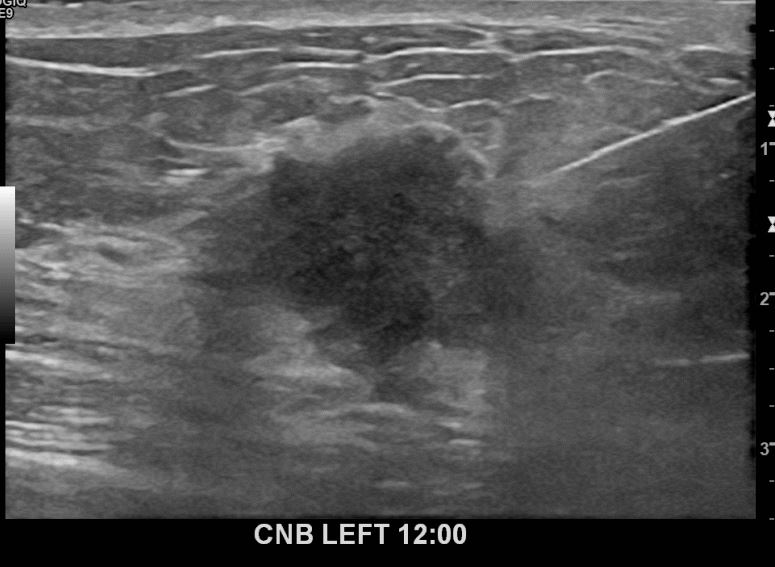

아산유외과개원후 672번째 유방암진단

상기환자 외부검사상 이상소견으로 내원하신 50대여성으로 좌측에 의심스러운혹 조직검사시행해 유방암 진단되었습니다.